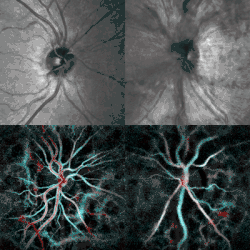

Papilledema (right) revealed by scanning laser ophthalmoscopy (top) and laser Doppler imaging (bottom). Healthy contralateral eye (left).